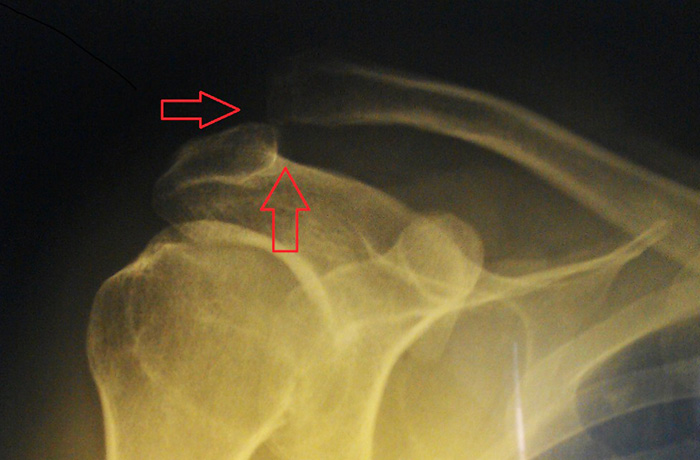

Из инструментальных методов диагностики информативной является рентгенография грудной клетки – на рентгенологических снимках обнаруживают вывих, оценивают степень смещения конца ключицы. Необходима правильная укладка пациента, так как от нее зависит результат рентгенографии.

- при осмотре – при вывихе со стороны ключично-акромиального сочленения акромиальный конец ключицы поднят вверх. Мягкие ткани в области вывиха опухшие;

- при пальпации (прощупывании) – пальпаторно обнаруживают опухлость и болезненность тканей. Характерным является «симптом клавши»: конец ключицы выпирает вверх, при нажатии такое выпирание исчезает, но если нажимание прекратить, то выпирание возобновляется.